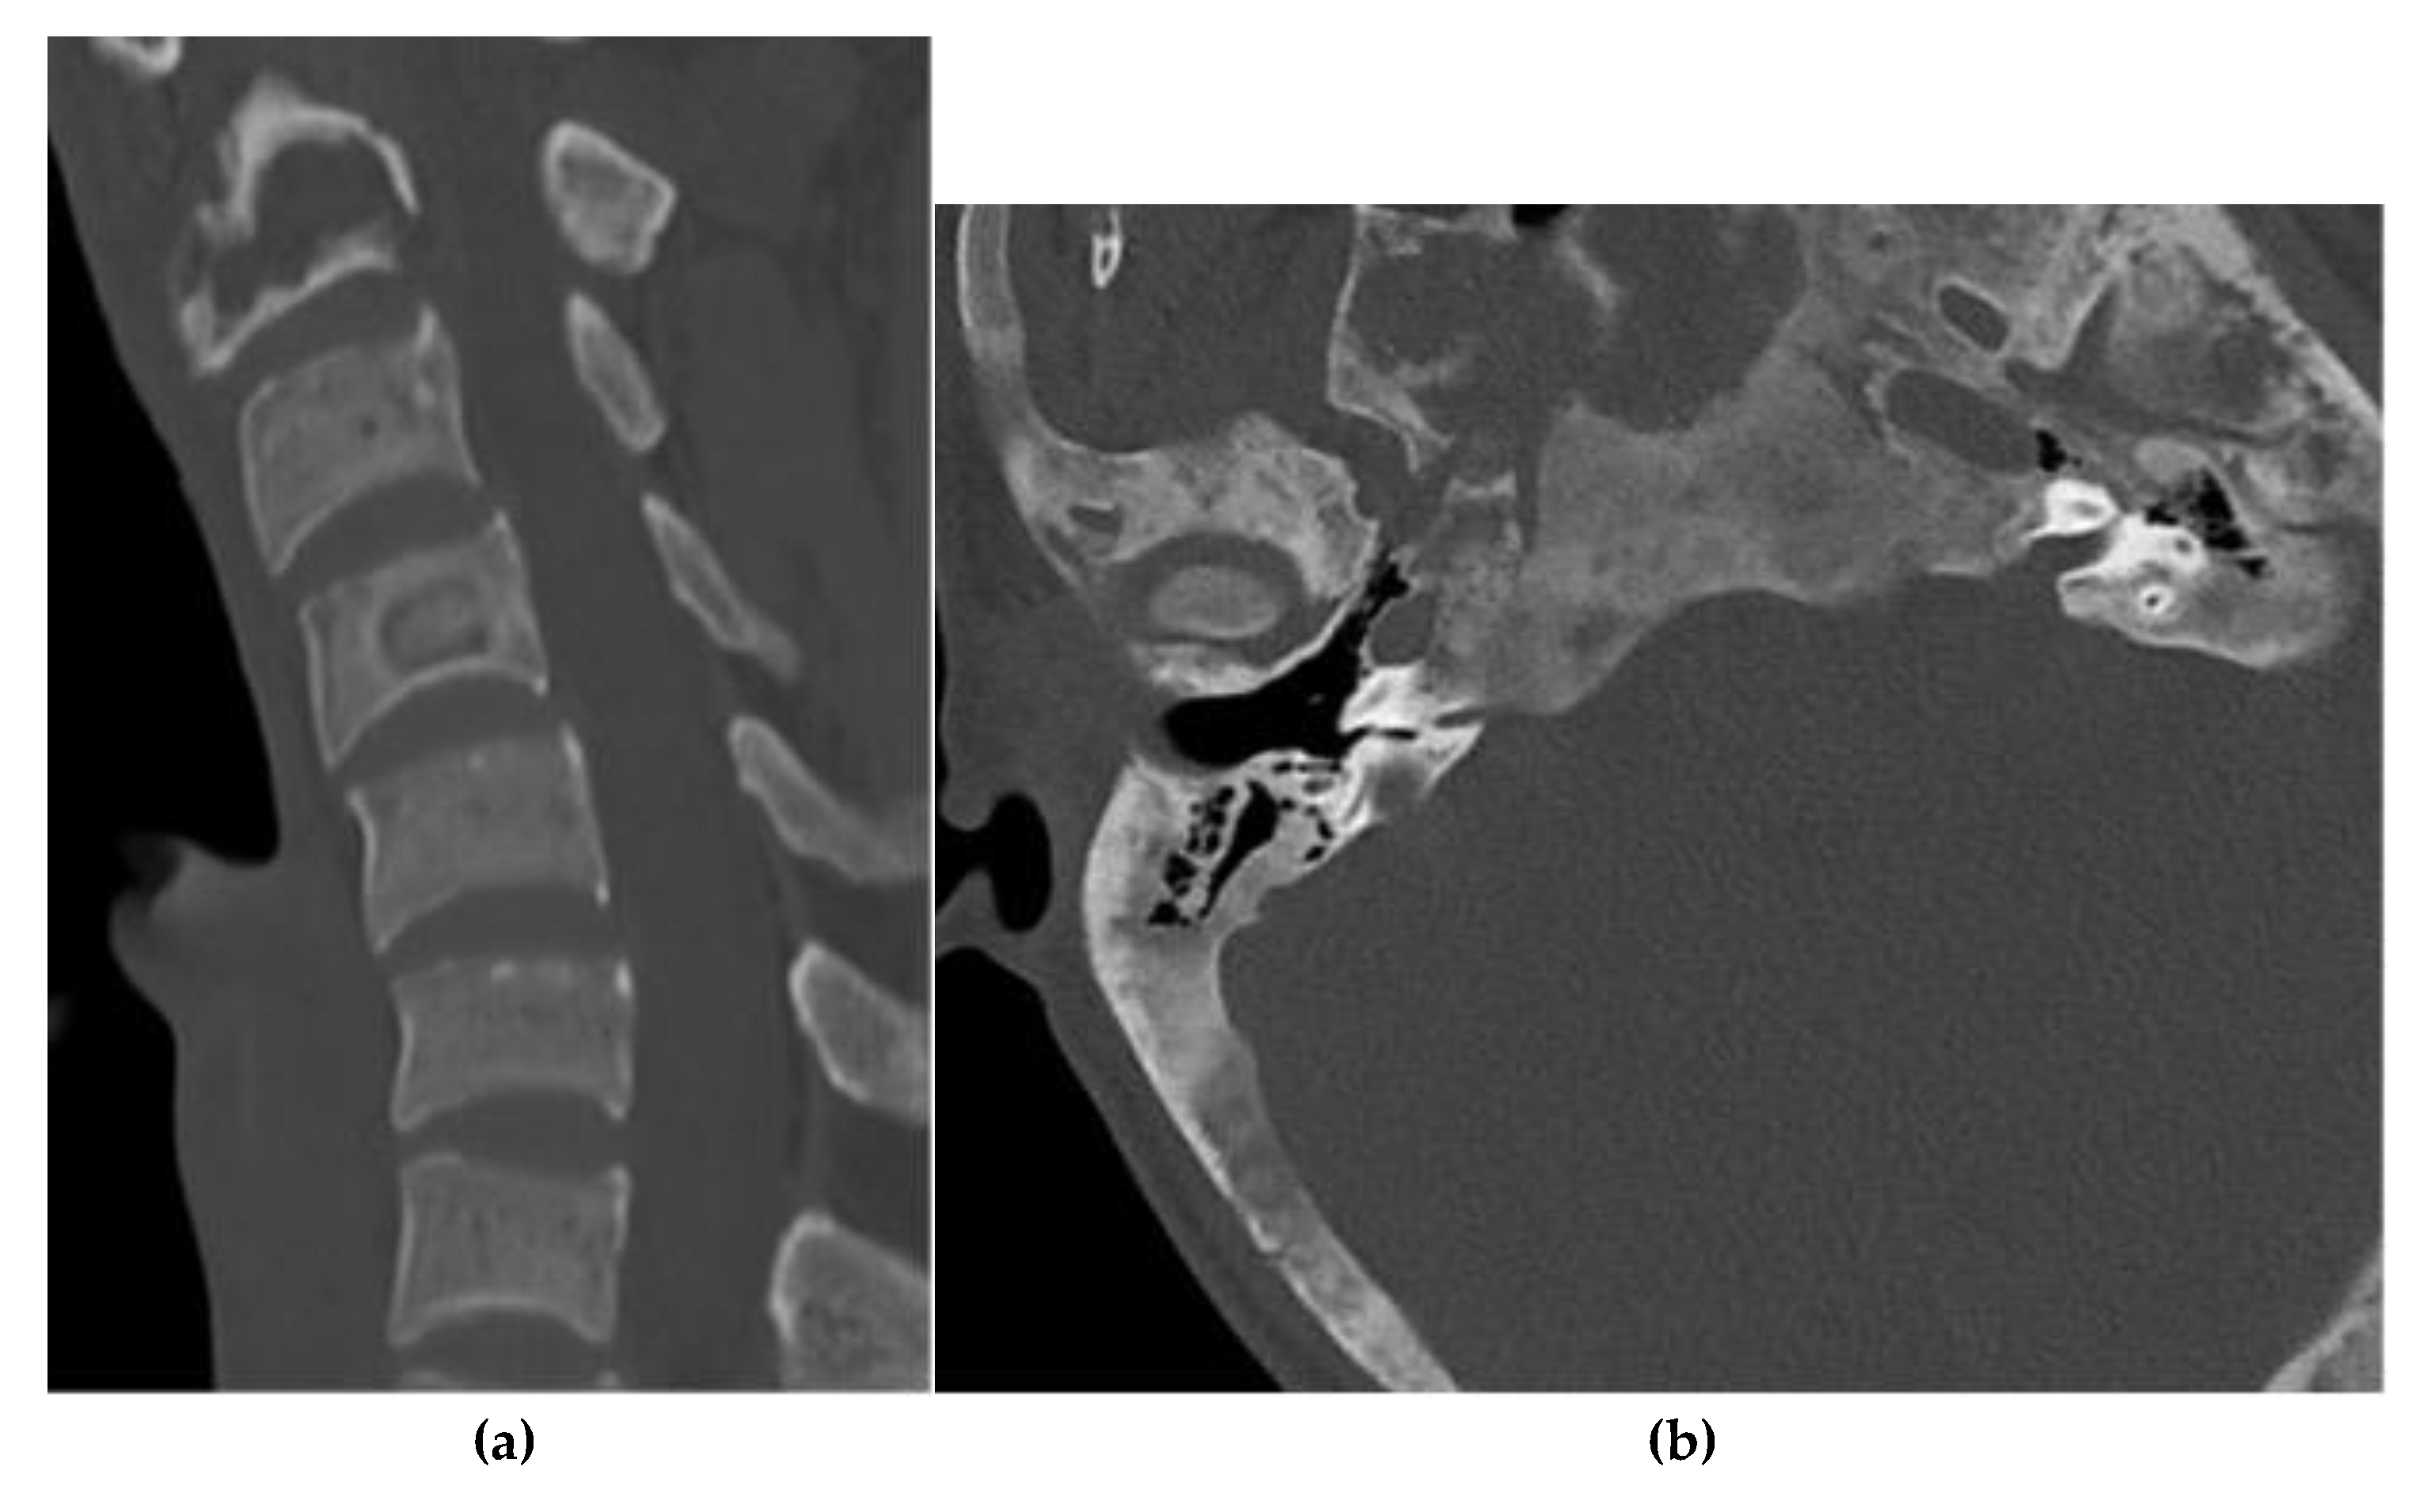

Osteochondroma